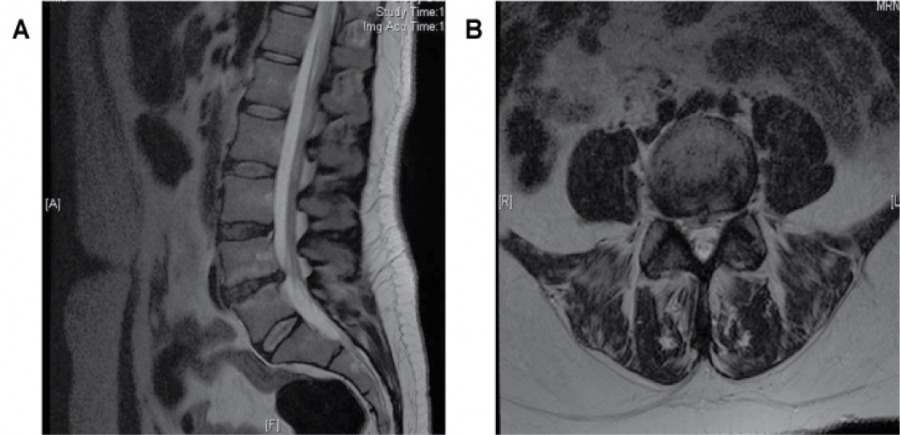

MRI of the lumbar spine with discs clearly visible. Note L4-5 discal degeneration.